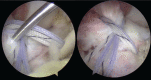

Arthroscopic techniques are considered the gold standard for treatment of displaced avulsion fractures of the anterior cruciate ligament. However, most arthroscopic surgical techniques and fixation methods are technically demanding and require removal of hard implant. This report describes a new, easy, safe, and all-arthroscopic method for reduction and fixation of displaced tibial intercondylar eminence fractures by using 1 anchor and 1 Pushlock.From January 2015 to June 2017, 8 adult patients with type II and III displaced tibial intercondylar eminence fractures were operated using this technique. Clinical assessment included patient demographics, cause of injury, delay before surgery, operation time, time to return to work and sport, International Knee Documentation Committee scores, and Lysholm knee scores.The average operation time was 48 minutes. The average follow-up period was 12.5 months. At the 6-month follow-up, all patients had acquired fracture union and complete functional recovery and were able to return to work. International Knee Documentation Committee objective scores and Lysholm knee scores were 92.4 (range 88-94) and 93.6 (range 90-96), respectively. At the last follow-up, anterior drawer, Lachman's test, and pivot shift tests were negative, and all patients had returned to their preinjury activity levels.Arthroscopic fixation by use of 1 anchor and 1 Pushlock is an easy, safe, and minimally invasive technique for treatment of displaced tibial intercondylar eminence fractures and does not require further surgery to remove fixation devices.Level of Evidence: Level IV, therapeutic case series.